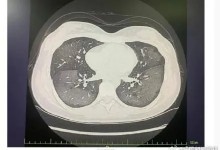

女子吸入防晒喷雾变白肺 医生提醒:不能直接对着脸喷-融党建互动平台

女子吸入防晒喷雾变白肺 医生提醒:不能直接对着脸喷

admin阅读(175)赞(0)

6月17日中午,20岁的绍兴姑娘丽丽(化名)打算和母亲一道外出吃饭逛街。为此,丽丽特地用上了新买的防晒喷雾(防晒倍数SPF50+、12小时持久防晒的蓝色防晒喷雾),该防晒喷雾号称针对青少年、学生,想着小孩子都能用,丽丽就更加放心,出门前...